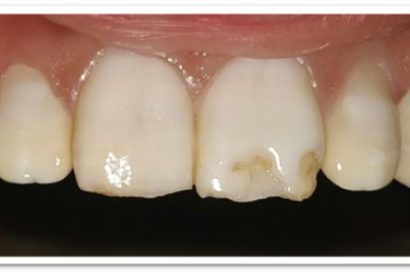

Patient Name:Saba Memon

Tooth Involved :11 , 21

Diagnosis : Ellis Class II Fracture

Treatment : Direct Composite Restoration Using Nanohybrid Composite

Before